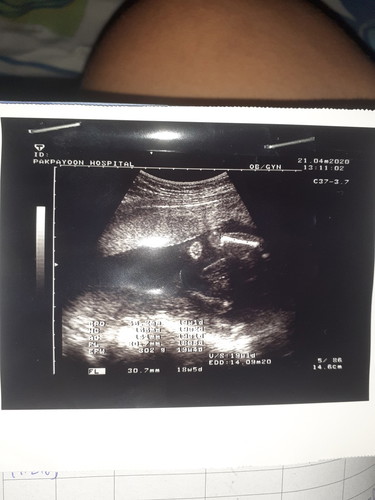

น่าจะเป็นส่วนขานะคะ